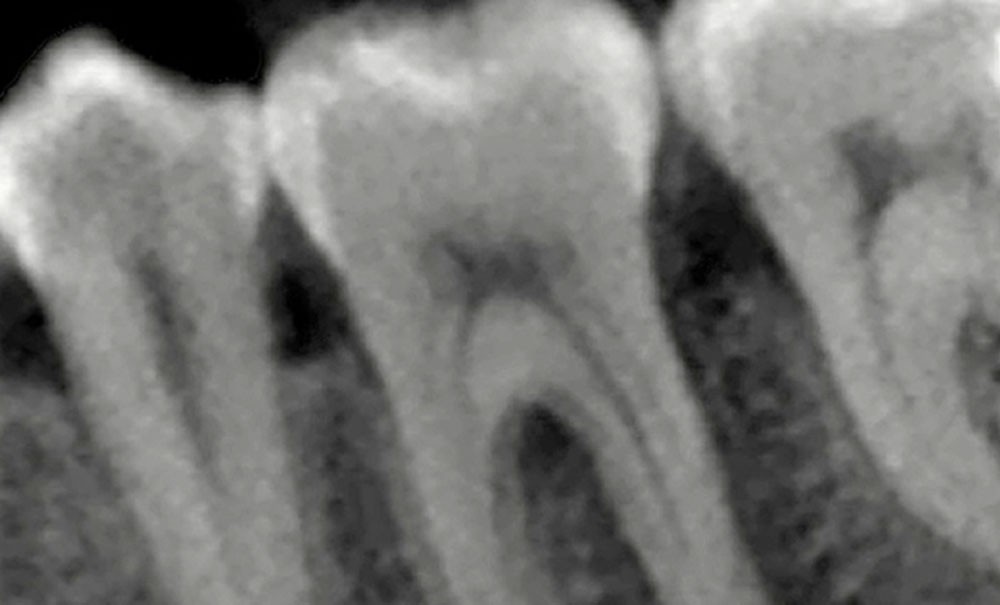

La compréhension de ces instruments, des biomatériaux et des différentes techniques est essentielle, et doit nous guider dans nos prises de décision en fonction des situations cliniques. Dans le cas clinique présent, suivi sur 24 mois, le patient se présente avec des douleurs à la mastication sur la dent 36. Tous les signes cliniques (test au froid négatif, test à la percussion positif, sondage parodontal positif en vestibulo-distal avec présence de fistule) et les examens radiologiques (LIPOE sur la racine distale, lésion inter-radiculaire) convergent vers un diagnostic de nécrose pulpaire due à une fracture longitudinale non complète (type 3 : Classification AAD) [1] (fig. 1).

La mise en forme doit également s’adapter aux singularités anatomiques. Pour ce cas clinique, le canal mésio-lingual a été mis en forme en premier jusqu’à la longueur de travail. Puis le test du cône a été réalisé (fig. 4 et 5) afin de voir si les deux canaux se rejoignaient. Ces deux canaux se rejoignant à 3 mm de l’apex, le canal mésio-vestibulaire a été mis en forme à sa longueur de travail moins 3 mm afin d’éviter la zone de confluence et le risque accru de fracturer un instrument. De plus, cette mise en forme longueur de travail-3 mm a son importance pour la précision de l’obturation et l’ajustage des cônes. Pour le canal distal, qui était un canal « en 8 », nous appliquons le même raisonnement que pour les canaux mésiaux, avec un canal principal, test du cône, et ajustage des maîtres-cônes (fig. 6).

Lors du suivi clinique et radiologique à 24 mois, nous observons une cicatrisation de la LIPOE, et la dent est asymptomatique (fig. 11 et 12).